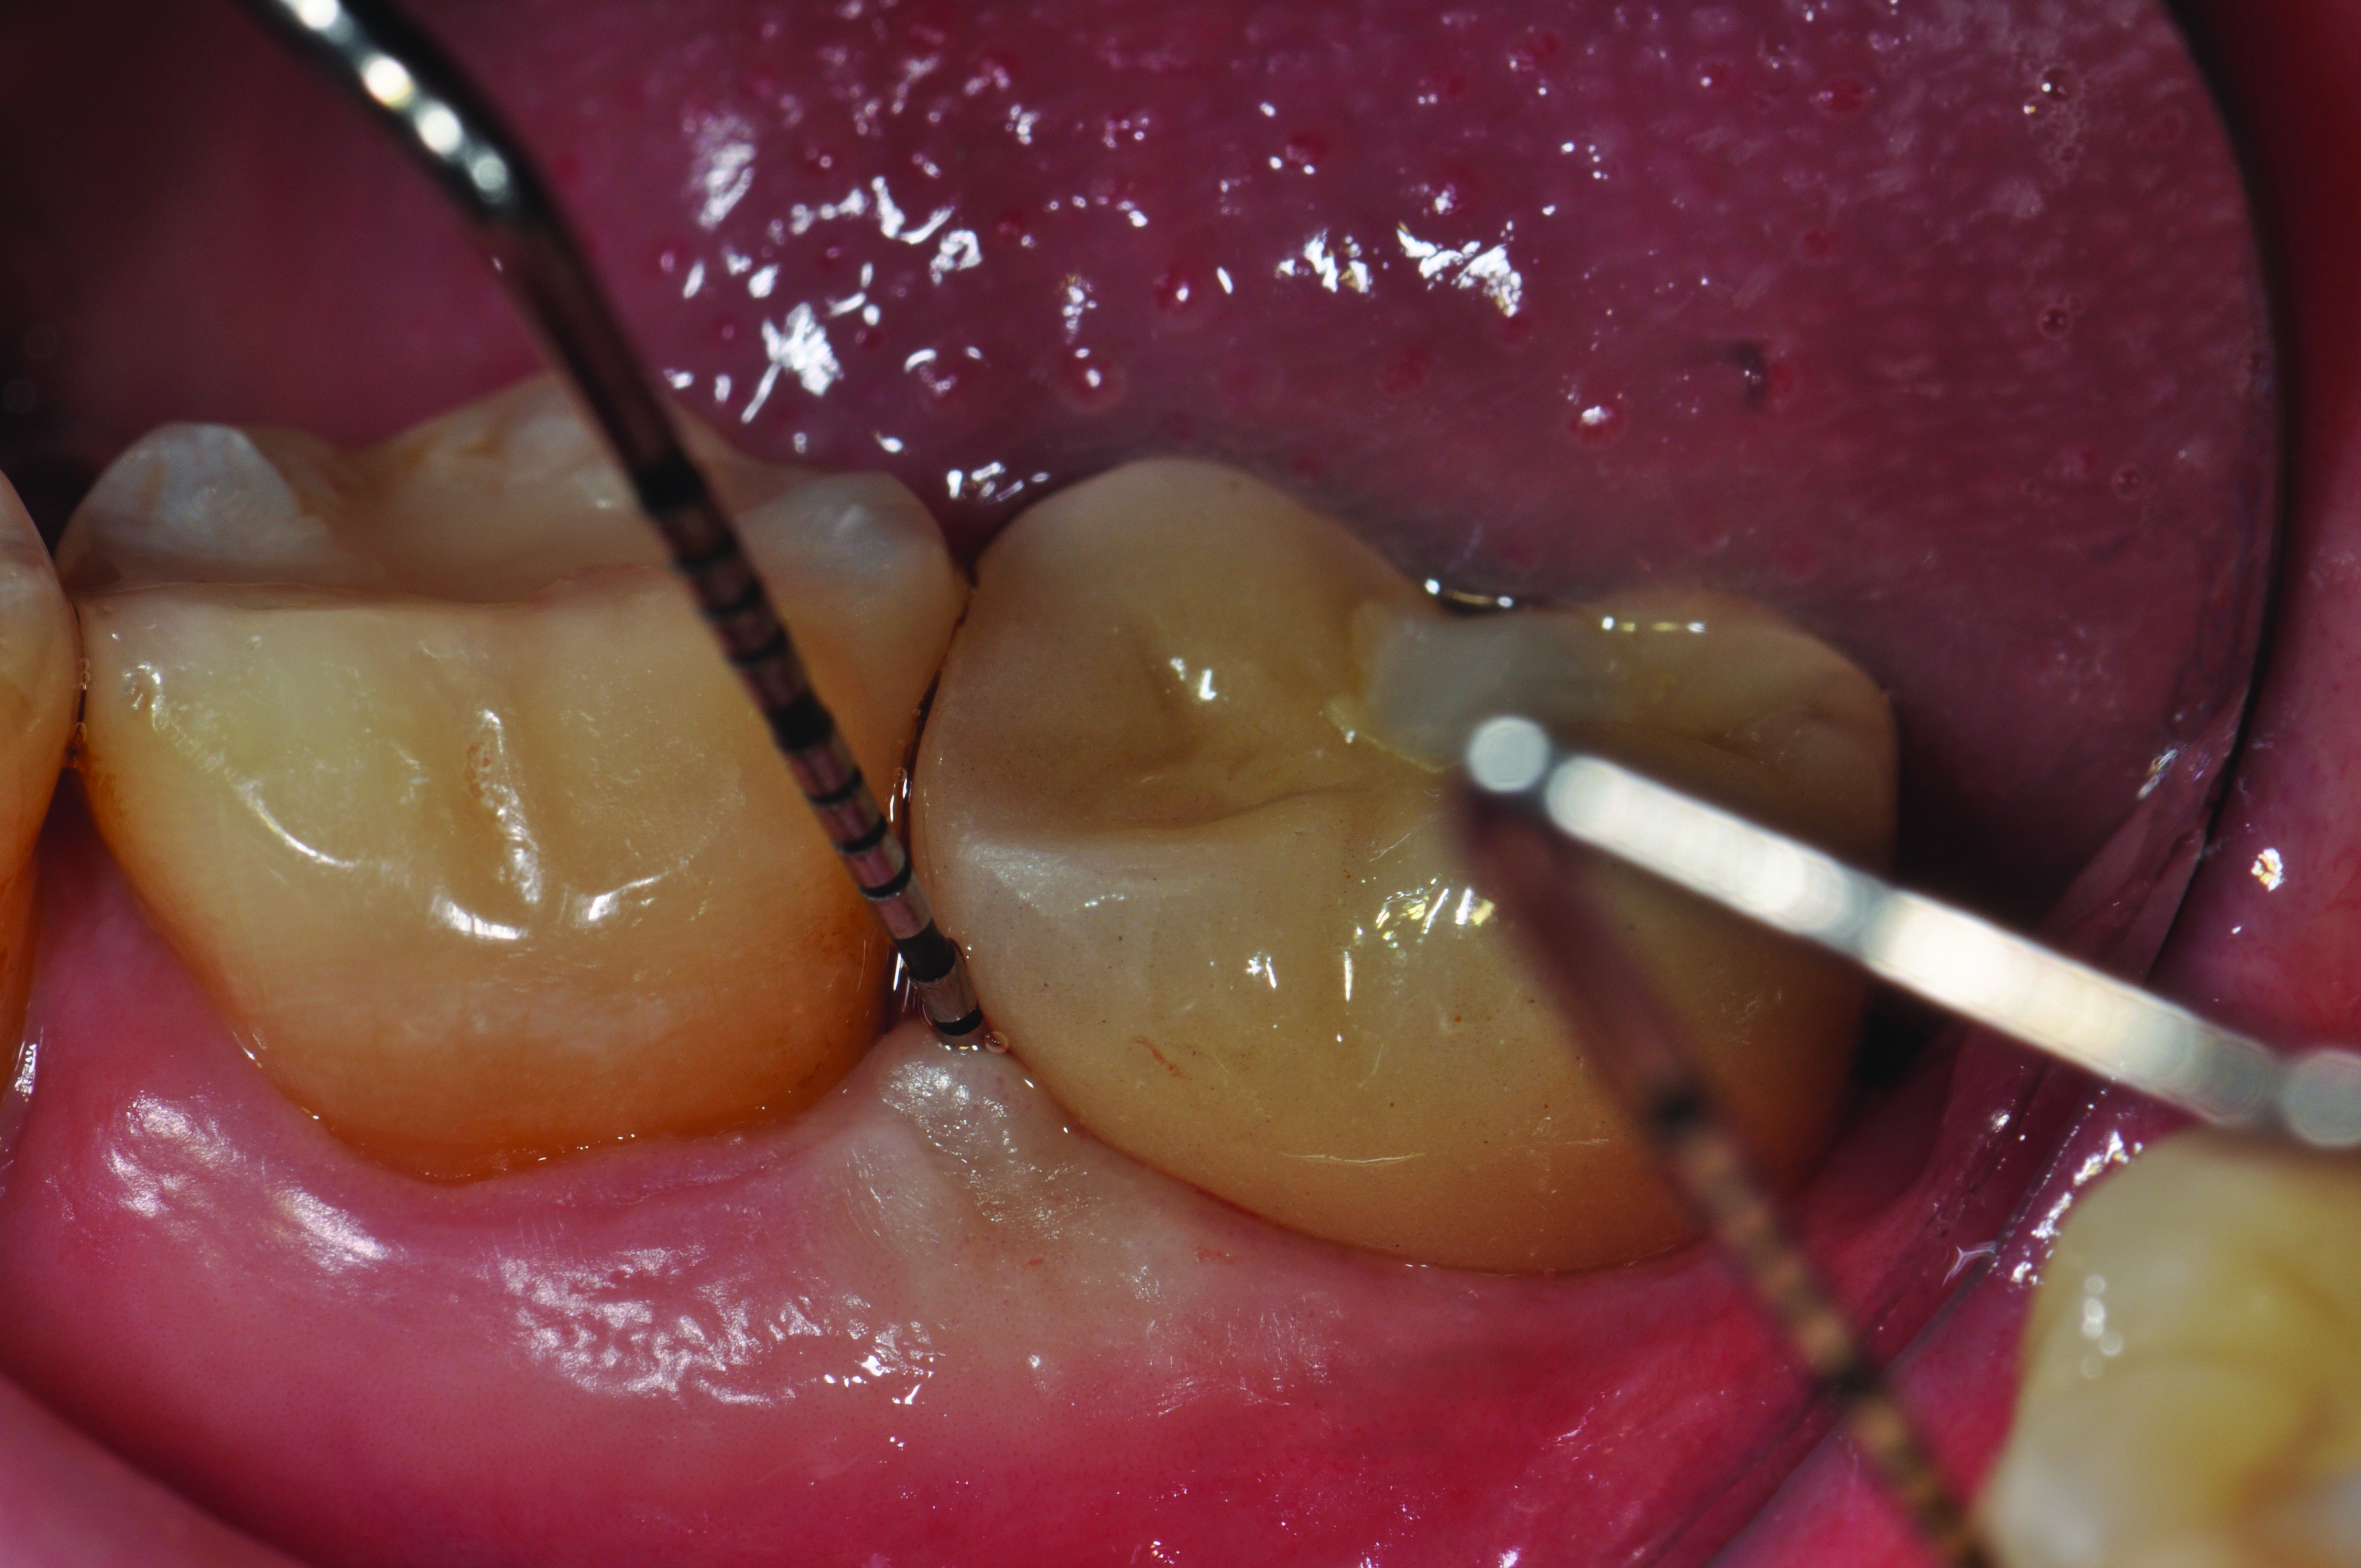

Clinical view of a maxillary left second premolar in an 73-year-old patient with a history of smoking. The tissue around the implant is quite inflamed and probes up to 8 mm with bleeding.

Figure 3